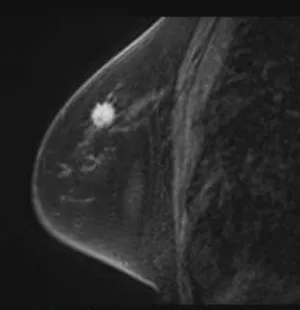

乳房造影MRI検査画像